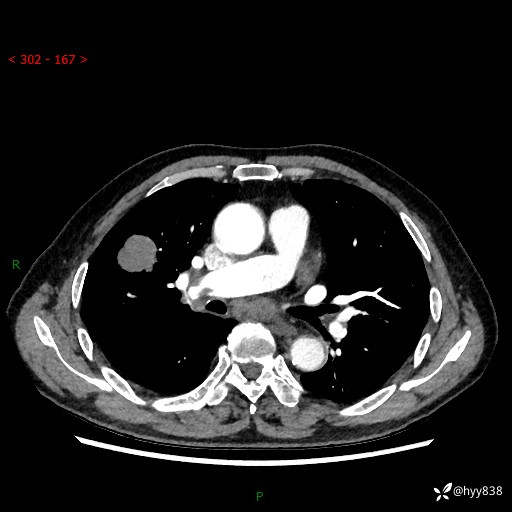

69岁/男,间断咳嗽伴气促、下肢水肿。临床拟诊肺栓,偶发肺均质强化结节--结果公布

【患者信息】:69岁/男

【主诉】:间断咳嗽伴气促、下肢水肿2周

【现病史及既往史】:患者2周来无明显诱因出现咳嗽,咳少量白痰,不易咳出,伴有气促,呈间断发作,症状与活动费力相关,以夜间为甚,不能平躺入睡,偶有憋醒,无胸闷胸痛、无发热、无头晕、头痛等不适,伴有双下肢中度水肿,就诊于当地县人民医院门诊,完善相关检查提示:左下肢深静脉血栓形成,未予以特殊处理,今患者为求进一步诊治来我院就诊,拟“心衰”收入我科。 起病以来,患者精神、饮食、睡眠可,大小便如常,体力明显下降,体重未见明显减轻。

【检查】:胸部CT增强